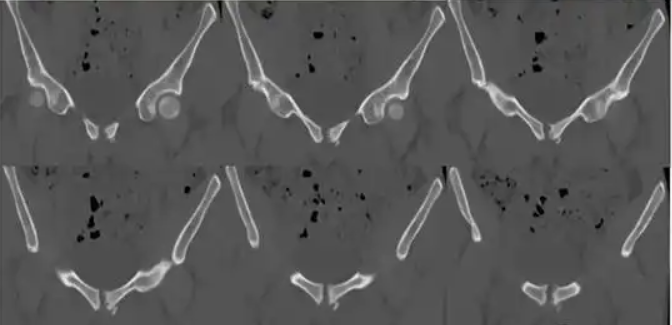

2.CT扫描

相比普通X线摄片显示更清晰,除清晰显示DR片所表现外,还可显示:死骨、间隙内游离多发碎裂小骨块 、耻骨联合关节面囊变及周围软组织情况。